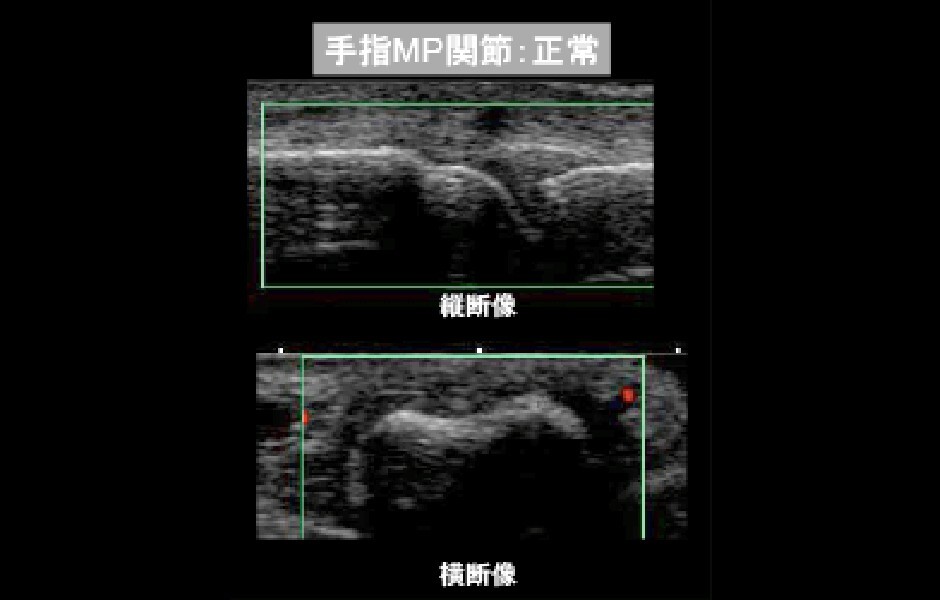

超音波検査

超音波検査では、グレースケールで滑膜が厚くなっていないか、滑液がたまっていないか、骨びらんがないかなどを確かめます。滑膜が厚くなっている部分ではパワードップラー法を用いて血流の状態を評価します。また関節だけでなく腱鞘の滑膜炎の存在も同時に観察することができます。

(パワードップラー法による関節腔内血流シグナル)